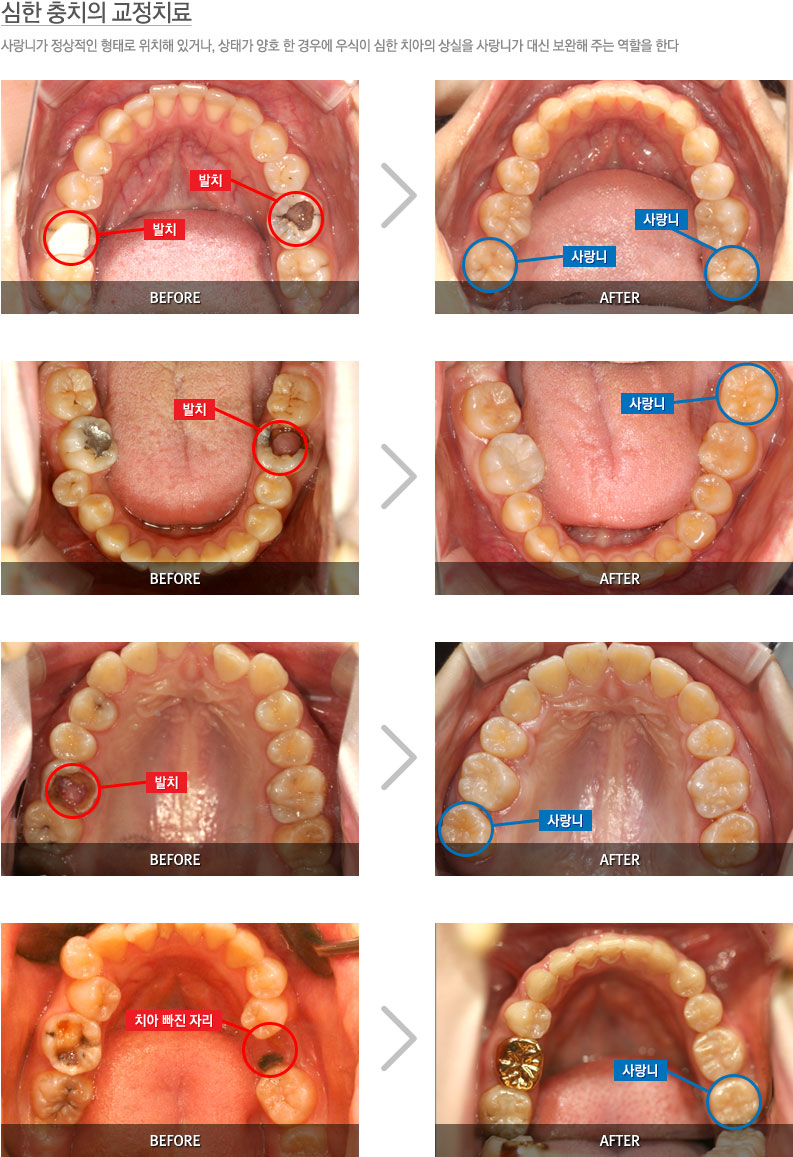

ÃæÄ¡Ä¡·á